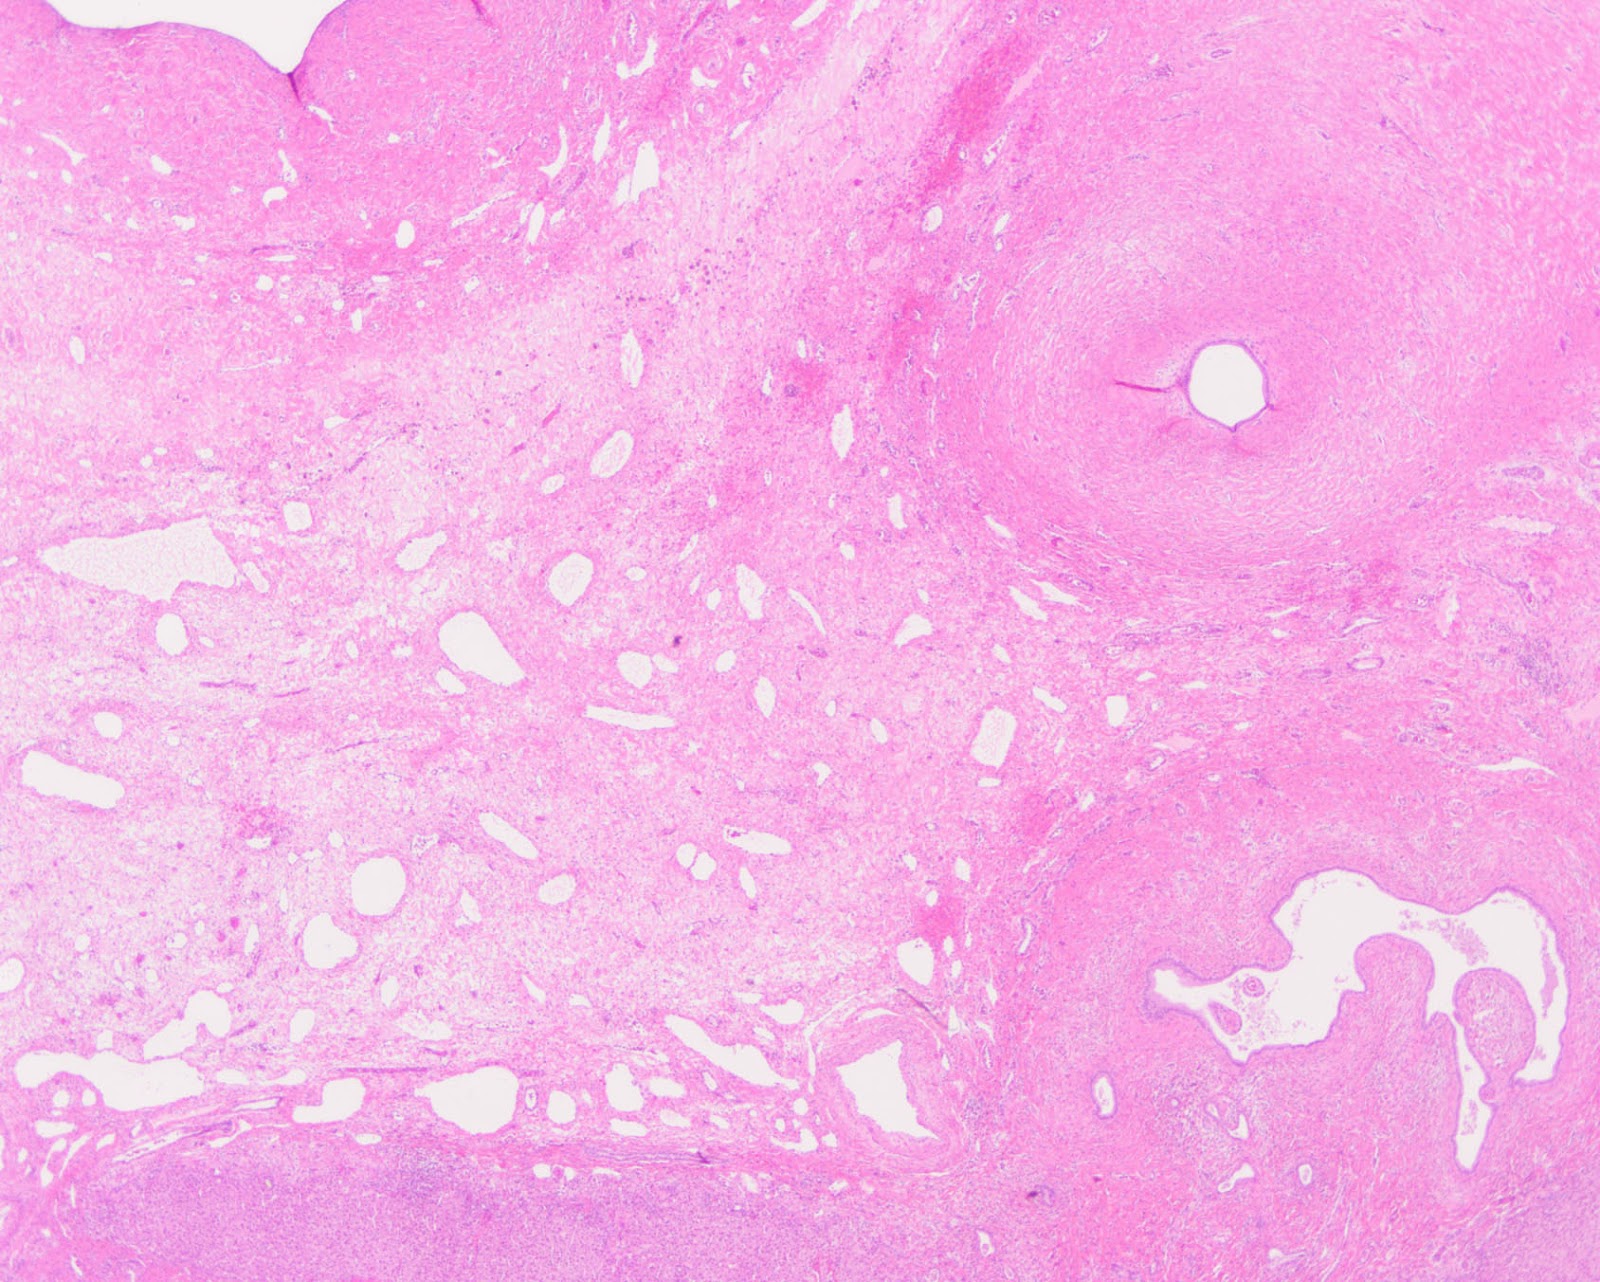

The patient underwent partial liver resection and gross examination showed an 18 x 17 x 5 cm, pink-purple cystic lesion. The cut surfaces were gray-white to pink-yellow with numerous cystic spaces up to 13.5 cm in greatest dimension and cross-sections revealing smaller intramural cysts (Figures 3 and 4). A portion of the specimen was sent for cytogenetic analysis, which failed due to lack of metaphase spreads. Microscopic examination revealed that the lesion was composed of a bland spindle cell population (Figure 5) within a variably loose, edematous, myxoid to hyalinized stroma with scattered ectatic thin-walled vessels, and occasional entrapped large biliary structures, the latter surrounded by dense concentric fibrosis (Figure 6). Grossly appreciated cystic structures were not lined by epithelium, and contained degenerated blood or bile (Figure 7), the latter often with xanthomatous reaction at the periphery (Figure 8). Cords of benign hepatocytes were prominent at the periphery of the lesion (Figure 9).

| Figure 7 |